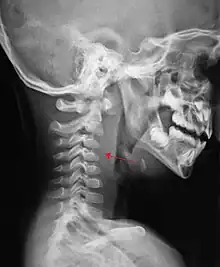

Large retropharyngeal abscess as seen on CT

A computed tomography (CT) scan is the definitive diagnostic imaging test.[4]